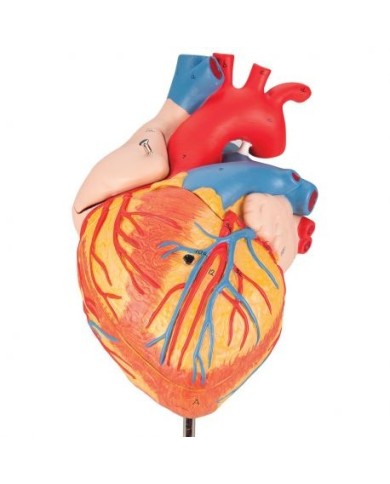

Modello di cuore di alta qualità scomponibile in 5 parti

Modello di cuore di alta qualità scomponibile in 5 parti

Modello anatomico di cuore, ingrandito 2 volte, su cavalletto

Realizzato in stampa 3D ad elevatissima risoluzione a colori.